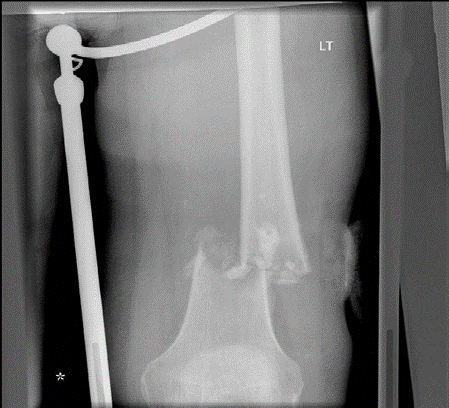

Lower limb Trauma Structured oral examination question 7 A 78-year-old woman fell out of her bed and sus- tai…

Lower limb Trauma Structured oral examination question 2 A 79-year-old woman fell in her garden sustaining th…